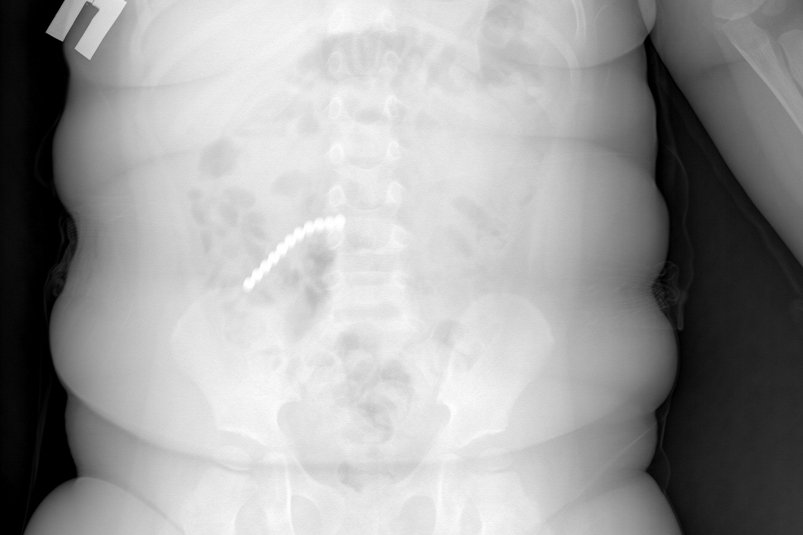

Ребёнок поступил в Приемно-диагностическое отделение ДРКБ в начале февраля с рвотой и ухудшением состояния. Рентген сразу показал десятки инородных тел в пищеварительном тракте — 20 магнитных шариков от неокуба. Врачи смогли извлечь 9 из них эндоскопически, но остальные переместились в кишечник и вызвали тяжелые осложнения.

Малыш в Бурятии проглотил 20 магнитных шариков. Фото: ДРКБ Бурятии